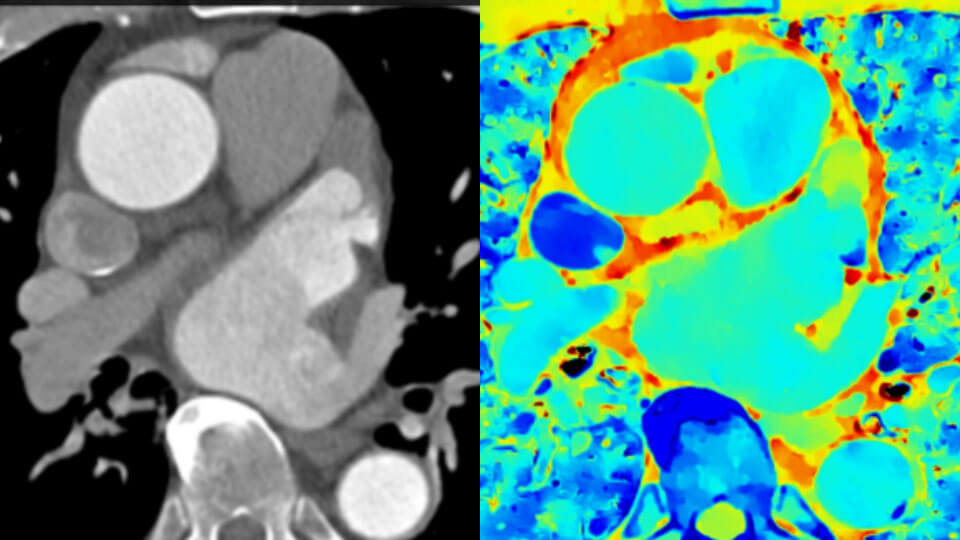

Agora, você pode facilmente ter tanto o “onde as coisas estão” da TC convencional combinado com o “como elas estão” revelado pelos dados do detector espectral. Camadas de dados espectrais ricos melhoram a caracterização e visualização dos tecidos e podem reduzir a necessidade de exames de acompanhamento para exames abaixo do ideal e achados incidentais.

Imagem de TC convencional (esquerda) Imagem de TC com detetor espectral (direita)